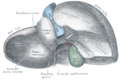

ان التشريح التقليدي للكبد يقسمه الى أربعة فصوص بناء على الشكل الخارجي.

فالرابط المنجلي المشاهد على السطح الأمامي للكبد يقسمه الى فصين يمين ويسار.

بينما يوجد من الخلف فصين أخرين أحدهما موجود بالأعلى ويسمى الذيلي والأخر الاسفل ويسمى الفص الرباعي .caudate and quadrate lobes

ويظهر من الخلف رابطين أخرين هماligamentum teres and ligamentum verosum

وهناك أيضا الشق العرضيtransverse fissure بالخلف والذي يفصل الفصين الذيلي والرباعي عن بعضهما البعض .